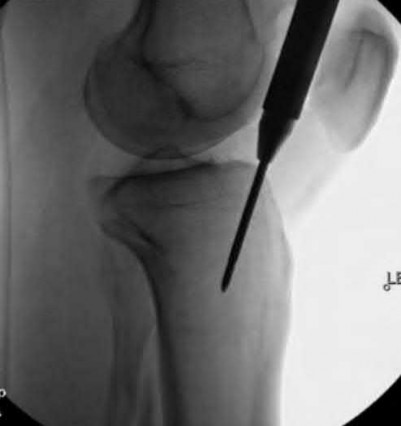

Question 1:

A 12-year-old obese boy presents with vague left thigh and knee pain. He is diagnosed with a Slipped Capital Femoral Epiphysis (SCFE) as seen in similar clinical scenarios. During percutaneous in-situ fixation, unrecognized penetration of the guide wire into the hip joint occurs. What is the most likely specific complication resulting from this technical error?

Correct Answer: Chondrolysis

Explanation:

Chondrolysis is a severe complication of SCFE characterized by rapid destruction of the articular cartilage. While it can occur idiopathically, its most established iatrogenic cause is unrecognized intra-articular hardware penetration. The 'approach-withdraw' fluoroscopic technique is required during pinning to assure pins are entirely intraosseous. Avascular necrosis (AVN) is usually due to damage to the epiphyseal blood supply (retinacular vessels) secondary to the initial displacement, forceful closed reduction, or posterosuperior pin placement.